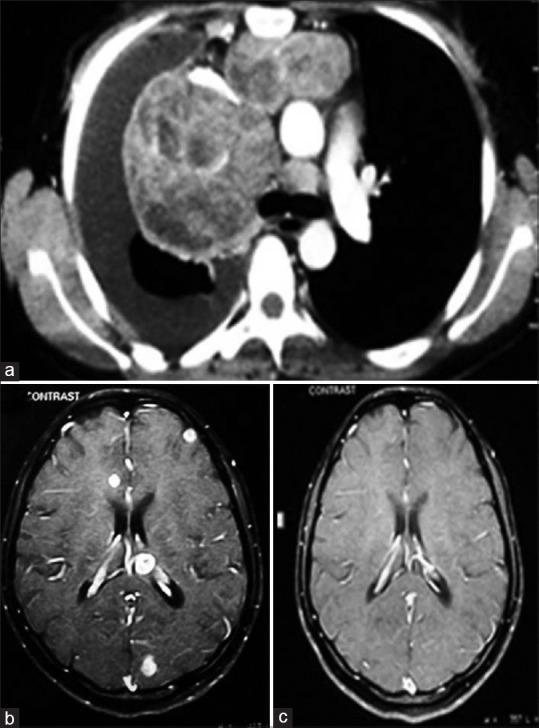

Mediastinal masses are commonly encountered in clinical practice. The commonly encountered anterior mediastinal masses include those of thymic or thyroid origin, teratomas, and lymphoma. Establishing the diagnosis by histopathology is essential considering the wide range of differential diagnosis and to exclude malignancies. Here, we present an unusual case of large mediastinal mass with chylothorax in a young immunocompetent female.